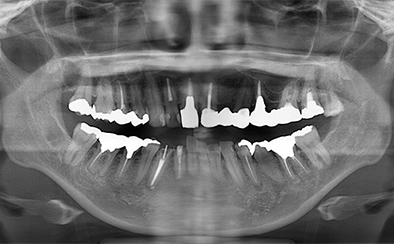

治療前

治療後

なるべく歯を残して、歯の神経も可能な限り保存し残していく方向で治療方法を検討しました。むし歯が大きく神経が侵されている歯は、抜髄を行い、精密根管治療の後にセラミックスクラウンを被せる治療方法を策定しました。患者さんのご希望と了解を得て治療を開始しました。

むし歯治療では、丁寧にむし歯だけを除去して健全な歯質だけを残します。名取歯科医院では、ラバーダムとマイクロスコープの使用が標準です。歯の根と神経の治療(根管治療)も行っていきます。

ラバーダムとはゴム製のシートで、治療する歯だけを露出させるように丁寧に切り取り、お口に装着します。唾液の中には天文学的な数の細菌が存在するため、一度治療した歯が再び悪化して再治療とならないためには、ラバーダムを装着し唾液や細菌に触れないように防湿を施した環境で治療することが何よりも大切で、歯科治療の基本です。歯の根元の黒い部分は膿の溜まった袋です。

むし歯が進行することで歯の神経まで細菌に侵されてしまった場合、昭和型の歯科治療では歯を抜いてしまう抜歯が当たり前でした。しかし、歯を抜いてしまうことで歯並びの乱れなど、ほかの歯への大きな影響があります。そこで自分の歯をできるだけ残すことを考えた「根管治療」や「保存治療」が選択されるようになってきました。

治療後の写真です。きちんと歯の根の治療(根管治療)を施すことで膿の袋も消失します。

歯ぐき(歯肉)の治療も大切です。歯ぐきを健康的な状態に治療していくことで、お口全体を審美的に優れた美しい状態に改善できます。このように歯ぐき(歯肉)の治療を行うことで、炎症を抑え、健康な状態をつくることができます。歯ぐきのコンディションを回復させると同時に、仮歯を入れます。しかしこれは治療中の隙間を埋めたり見た目を取り繕う「仮歯」とは異なります。プロビジョナルレストレーションと言い、最終的な歯(本歯)と同じ形体をもつ歯で、治療した歯や周囲の歯、反対側の歯、歯ぐきなどお口全体の回復と調和を整える大切な治療プロセスです。もちろんこの期間に仮歯での噛み合わせ、咀嚼や嚥下、または発音や発語など機能的な回復に不具合がないか、顎関節への影響や負担がないか検証する期間でもあります。

仮歯で機能回復の確認を行い、そしてさらに微調整を行います。機能的・審美的に改善を確認できた仮歯の形態を元にセラミックスクラウンを作製します。熟練した歯科技工士によるセラミックス制作を行い、装着後に最終的な微調整(咬合調整)を施し、むし歯治療、歯の根の神経治療(根管治療)、白いセラミックスによる修復治療のすべてが終了しました。

| 費用 | ジルコニアセラミック24本:5,280,000円 根管治療(小臼歯5本):770,000円 根管治療(前歯6本):792,000円 合計:6,842,000円 |

|---|---|

| リスク・副作用 | 治療中に一時的な咬合痛や冷温水痛、若干の歯肉の腫れ、発赤などを生じることがあります。また仮歯の時期には仮歯の脱離や破損の可能性、舌感などに違和感を覚えることがありますが、本歯に移行するまでに通常消失します。 ※すべて症例による違いや個人差があります。 |

※表示金額は全て税込みです。